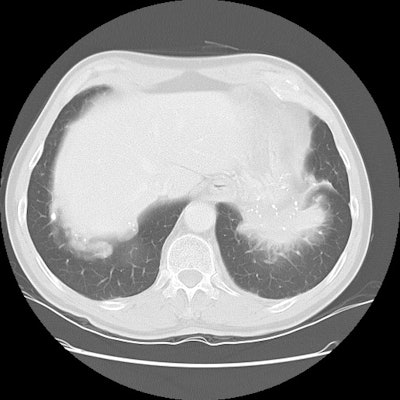

The patient shown on the CT images below presented for evaluation of an enlarging abnormality on CXR. The CT demonstrates exuberant pleural plaque disease along the right diaphragmatic surface. There is a soft tissue mass within the left lower lung that contains a large eccentric calcification. Lung markings radiate into this lesion from the adjacent lung parenchyma and there is distortion of the major fissure. The finding suggested rounded atelectasis, however, the lesion had more aggressive features more inferiorly (see lower CT images). PET images are shown below CT's.

A PET-FDG scan was performed to determine if the lesion demonstrated increased metabolic activity. The lesion appeared as a region of decreased activity above the surface of the left hemidiaphragm. This finding suggested the lesion to be rounded atelectasis which has been shown to not be metabolically active on FDG-PET imaging. The patient had the lesion surgically resected and it was found to be rounded atelectasis and pleural plaque.